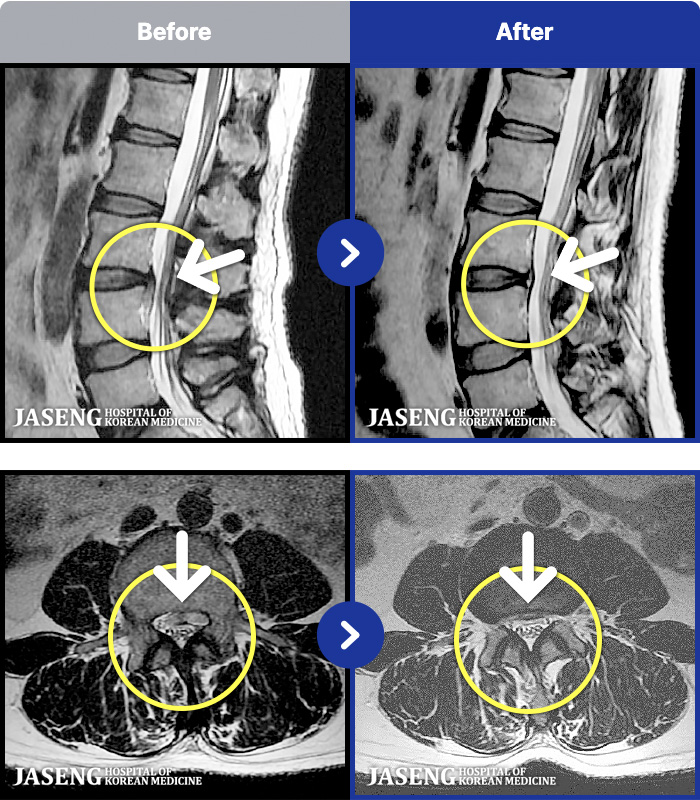

1,257 MRI ũ ʸ Ȯϼ.